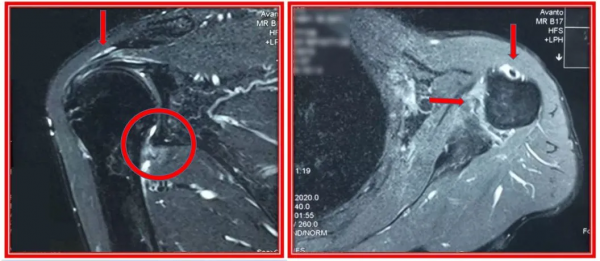

江主任迅速給王阿姨安排了肩關節 X 光片及核磁檢查。慢慢地,一個肩關節隱形殺手的真面目逐漸暴露在大家面前——肩袖鈣化性肌炎。

上圖為一例嚴重肩袖鈣化性肌腱患者X光片,紅色箭頭所指為鈣鹽沉積